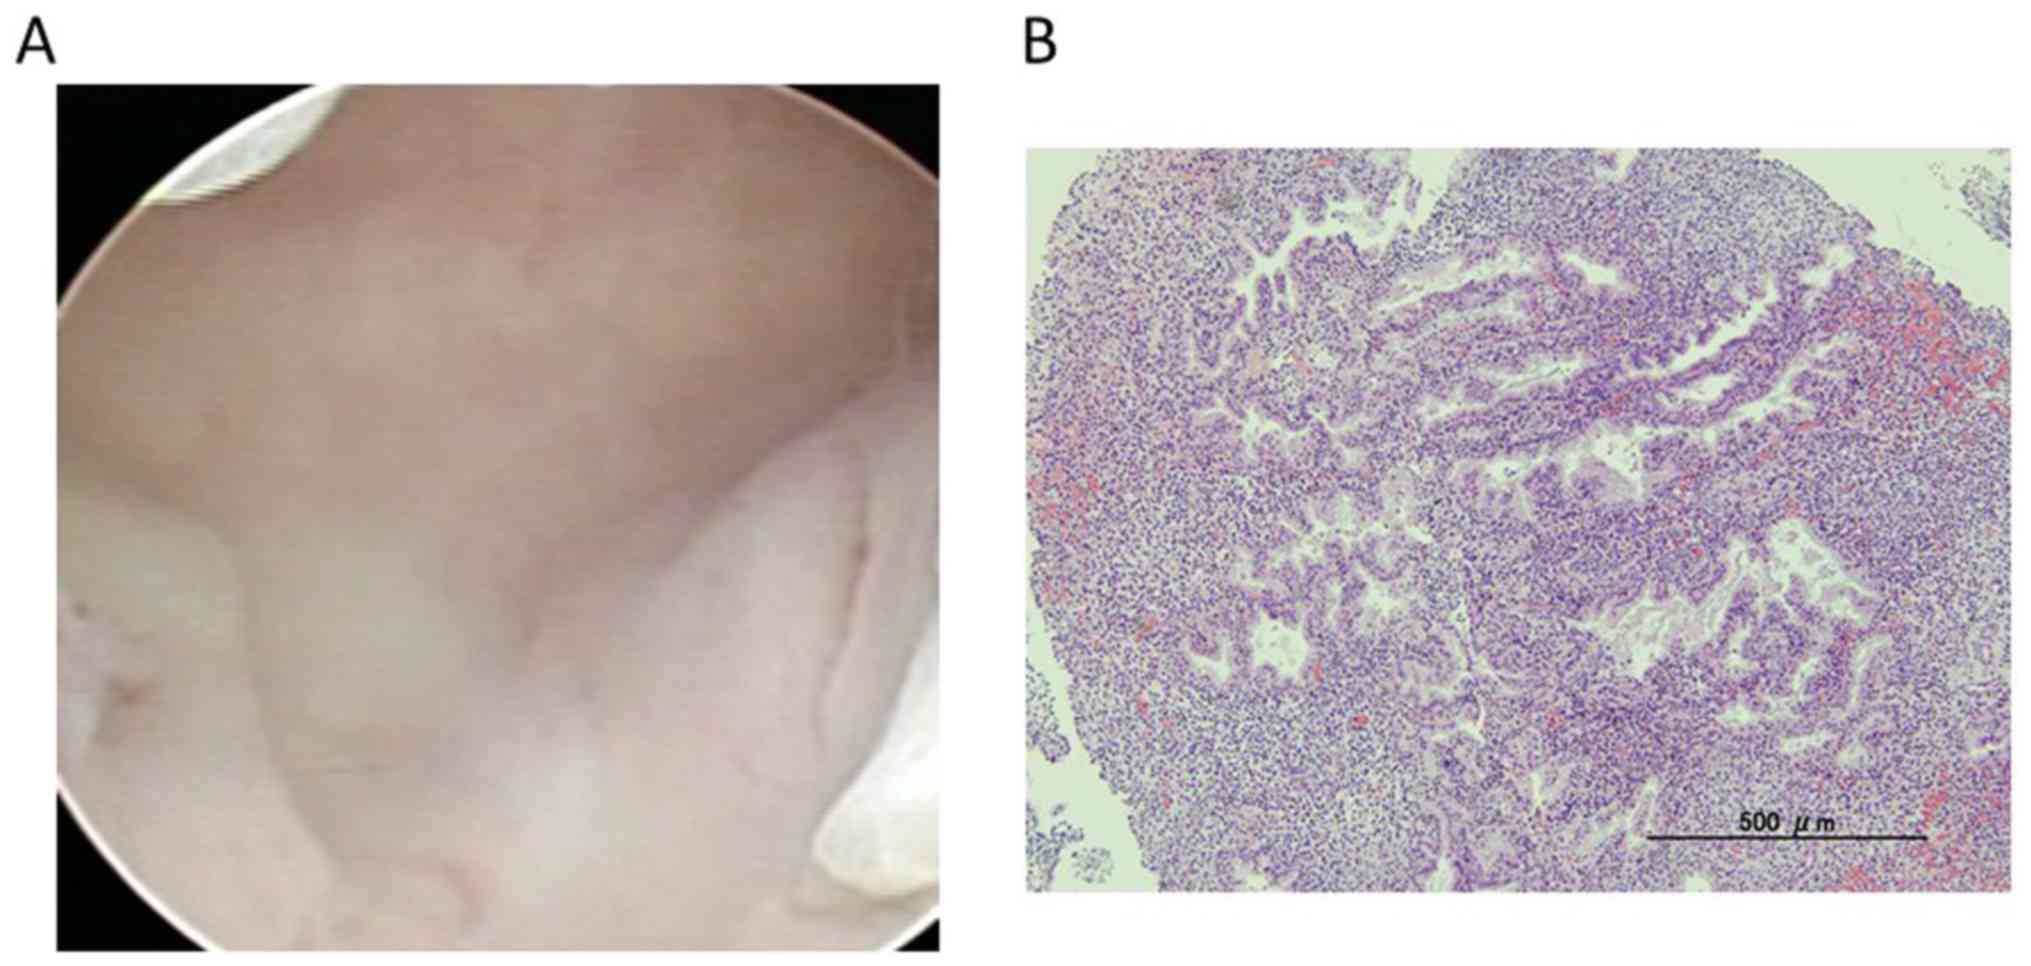

Figure 3

Hysteroscopic findings of the uterine cavity. (A) There was no apparent malignant endometrial lesion in hysteroscopy during hospitalization. The small endometrial polyp was detected using hysteroscopy. (B) Histological findings of the polyp biopsied by hysteroscopy during hospitalization.